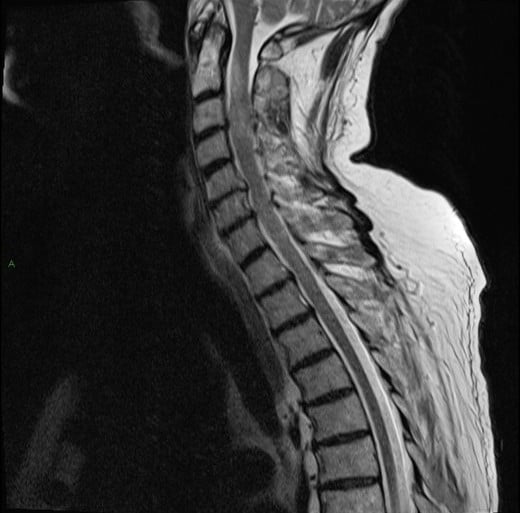

U tủy sống

» Thông tin: Nam giới – 70 tuổi.

» Lâm sàng: Yếu vai phải.

# U sao bào tủy sống (Spinal Astroctyoma) ngang mức C2-C4.